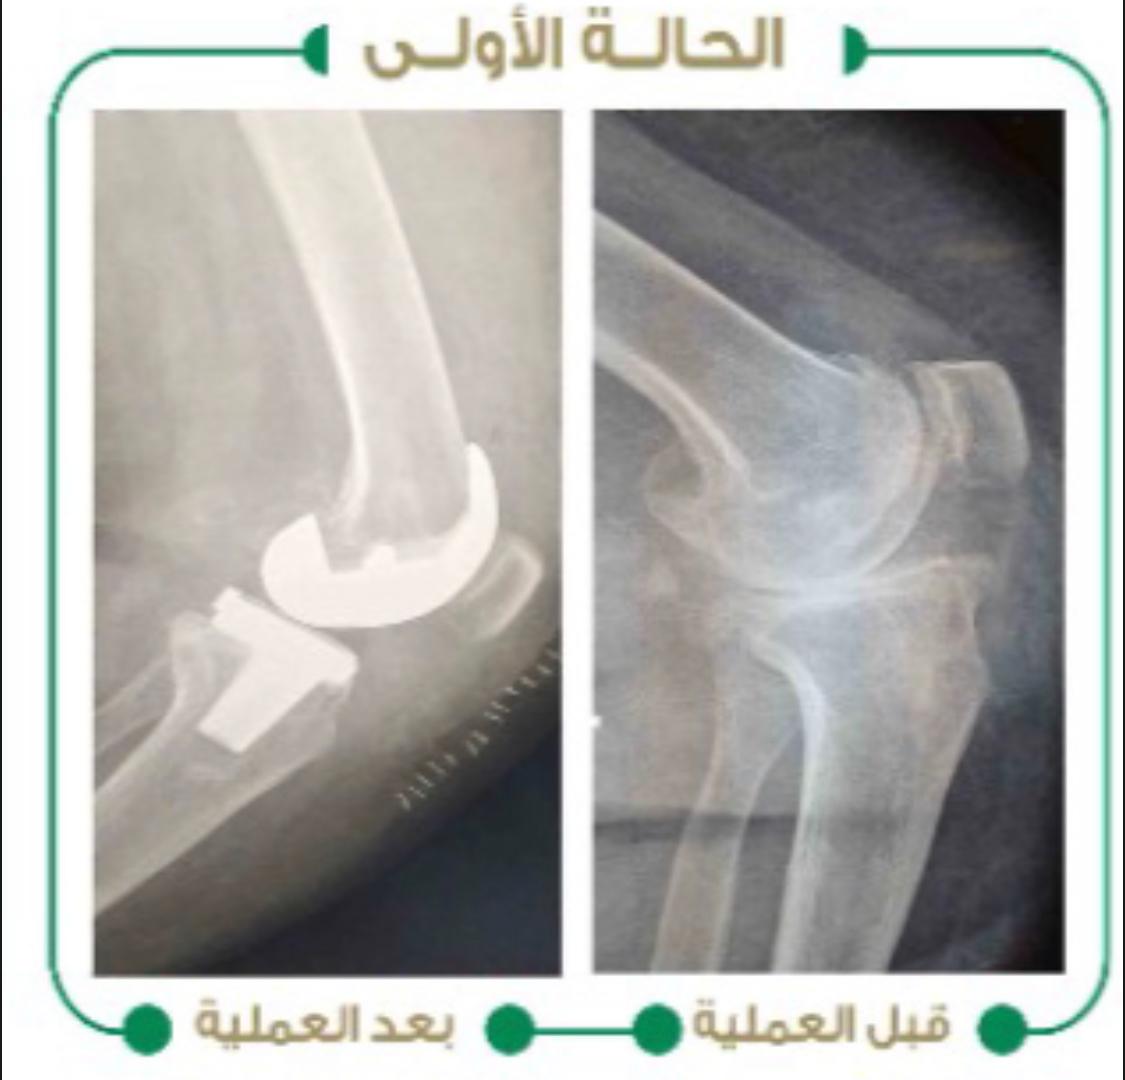

نجح بفضل الله فريق جراحي متخصص في جراحة العظام والمفاصل في مستشفى وادي الدواسر العام، في إجراء عمليتين جراحيتين لمريضين يعانيان من خشونة متقدمة في مفصل الركبة وتقوس شديد مع إرتخاء في الأربطة للركبة وصعوبة في المشي والحركة، حيث تم إجراء عملية تغيير المفصل بمفصل آخر صناعي ومعالجة التقوس، فيما بدأ المريضان مرحلة العلاج الطبيعي والمشي في نفس يوم العملية ولله الحمد.